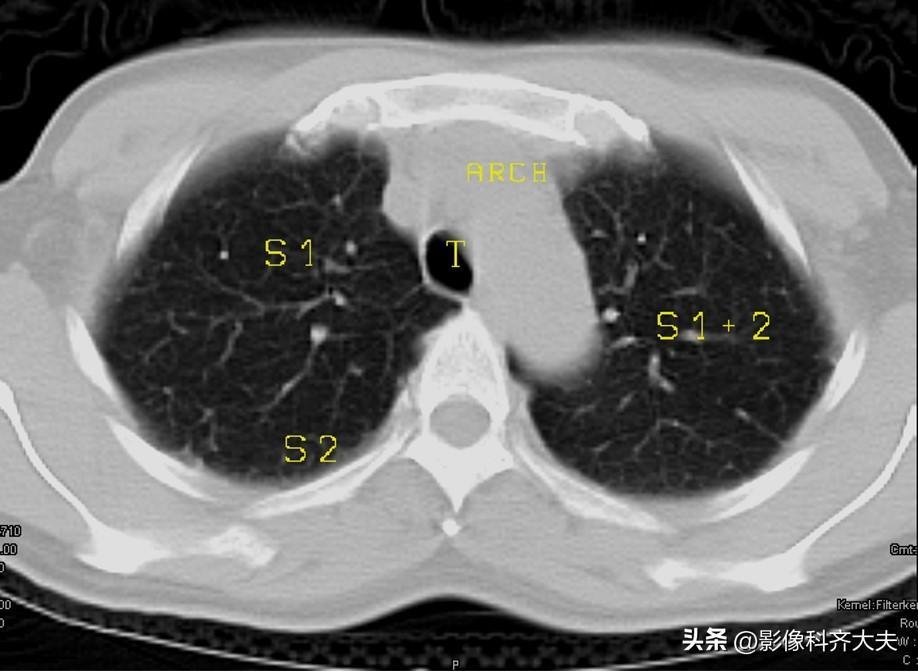

图2:主动脉弓层面

▲ARCH :主动脉弓,S2:上叶后段,S1+2:左上叶尖后段